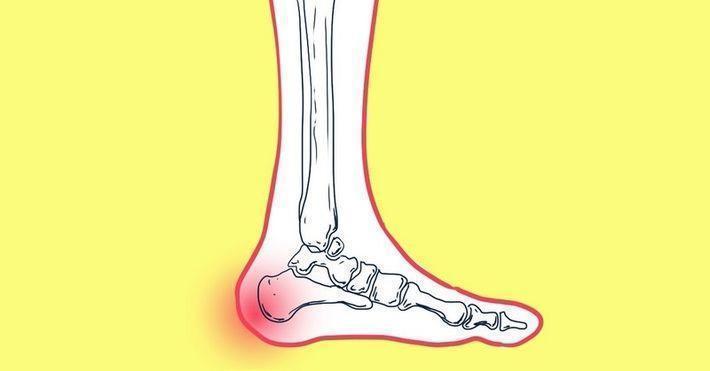

Мочевая кислота является продуктом распада пуринов, которые содержатся во многих продуктах. В норме — основное количество мочевой кислоты должно выводится с мочой. Если же почки по тем или иным причинам не справляются с ее выведением, она накапливается в организме. На первых этапах высокий уровень мочевой кислоты не вызывает никаких проблем и не имеет ярко выраженных симптомов. Тем не менее со временем это может привести к образованию камней в почках, подагре или почечной недостаточности.

Лечения подагры — длительный и трудоемкий процесс, в котором результат во многом зависит от терпения и дисциплинированности больного. Полностью излечиться от заболевания невозможно, можно только облегчить состояние человека, и снять воспалительный приступ.

Подагра — древнейшее заболевание, причняющее человеку массу неприятностей. Это заболевание характеризуется нарушением обмена веществ, при котором в организме накапливается большое количество мочевой кислоты. Приступы подагры приводят к жутким страданиям. Но от этого может спасти правильное питание.

Питание при подагре

Как только происходит нарушение пуринового обмена, у человека начинается подагра. Количество мочевой кислоты в организме просто зашкаливает. Такой процесс приводит к тому, что в околосуставных тканях начинают скапливаться ураты. А главная проблема в том, что процесс не ограничивается только суставами: отложение уратов происходит и во внутренних органах, особенно в почках.

Что такое подагра?

Прежде чем узнать, какие продукты нельзя употреблять при подагре, следует рассмотреть, что это за недуг. Чаще всего данным заболеваниям подвержены мужчины и женщины после сорока лет, хотя ранее считалось, что подагрой болеют исключительно мужчины. Это одна из разновидностей болезней суставов, причиной развития которой является злоупотребление продуктами с высоким содержанием пуринов. Именно из-за их употребления откладываются соли в суставах. Болезненные ощущения, имеющие форму длительных приступов, могут поражать суставы и верхних, и нижних конечностей. Симптоматика крайне неприятная – отечность, деформация суставов, воспалительные процессы, острые боли.